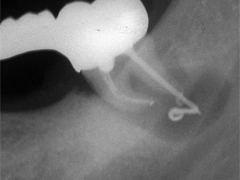

Dieser Zahn wurde schon geraume Zeit zuvor von einer Kollegin im Notdienst eröffnet und anschlies­send mit einer aufwendigen Amal­gamrestauration ästhetisch an­sprechend wieder verschlossen. (Bild 1) Uns blieb noch WK/WF, was bei massiver Überstopfung der hin­teren Wurzel auch gelang (Bild 2).

"Überstopfen ist immer noch besser als Unterstopfen" laut Koçkapan. OK, hier wurde des Guten aber ganz eindeutig zuviel getan.

Also direkt neben dem Zahn das Zahnfleisch ein wenig angehoben und zur Seite gedrängt und dann mit einem scharfen Löffel den Überschuss vollständig entfernt.

Schon 8 Monate später ist eine deutliche Verbesserung der Gesamt­situation unverkennbar (Bild 3). Verlorengegangene Knochensubstanz wurde in Teilen schon wieder aufge­baut, doch ist noch gar nichts entschieden. Schaun mer also ma'.

Abrechnungstechnisch hat der Mut zur WR an 38 gefehlt, deshalb nur EXZ1.